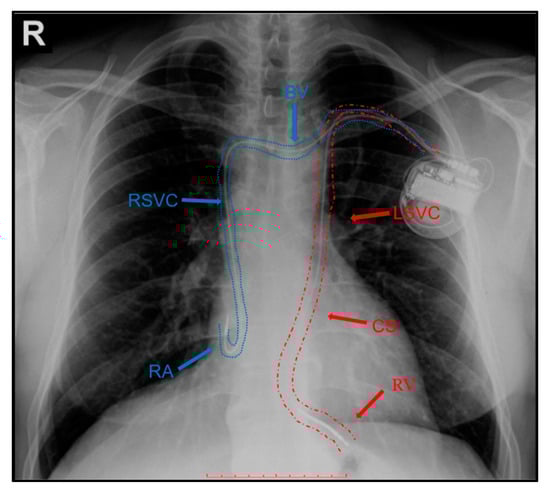

2. Case Report